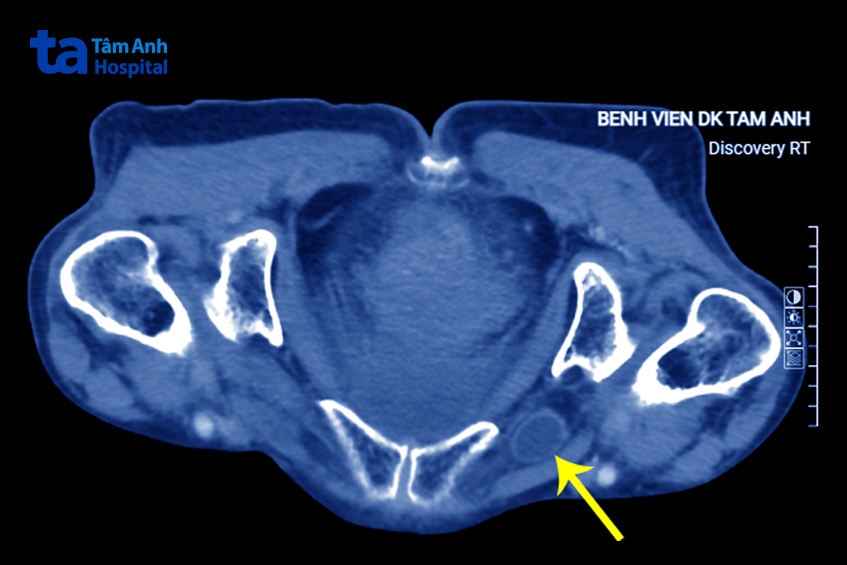

Trường hợp bà Thoa, may mắn được cấp cứu kịp thời tới bệnh viện chuyên khoa sâu, nên phát hiện bệnh sớm. Bác sĩ Minh đánh giá quai ruột thoát vị bịt chưa hoại tử, còn ngấm thuốc trên phim chụp CT, chỉ định bệnh nhân mổ nội soi.

Khi nghi ngờ, nhất là trên phụ nữ lớn tuổi, có thể trạng gầy nhỏ, bác sĩ có thể chỉ định chụp cắt lớp vi tính CT khi đã loại trừ thoát vị bẹn và đùi. Phim chụp CT cho phép bác sĩ chẩn đoán thoát vị bịt trước mổ lên tới 90% nhờ thấy rõ quai ruột chui qua lỗ bịt, quai ruột non giãn, có hình mức dịch-khí, điểm chuyển tiếp ở lỗ bịt.